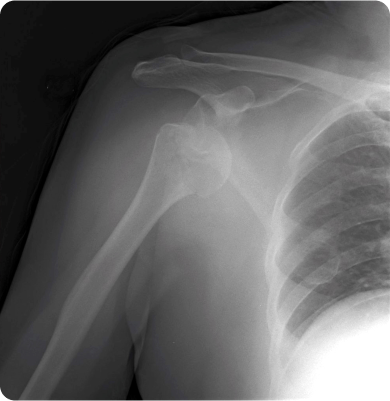

어깨 관절을 둘러싼 관절막이 퇴행성 변화를 일으키면서 염증을 유발하는 질환

주로 40~60대에 발생하며 어깨를 오래 사용하지 않거나 움직임이 제한될 때 관절이 굳어 생기거나 당뇨병 등 기저질환이 원인이 됩니다.

어깨 관절을 감싸고 있는 회전근개 힘줄이 손상되거나 찢어지는 질환

어깨를 움직일 때 어깨뼈와 힘줄이 충돌하여 염증과 통증을 유발하는 질환

팔을 반복적으로 머리 위로 들어 올리는 동작이나 잘못된 자세, 외상, 나이로 인한 퇴행성 변화 등이 원인이 됩니다.

어깨 관절이 반복적으로 빠지는 상태가 습관처럼 지속되는 질환

처음 발생한 어깨 탈구 이후 관절이 불안정해지거나 선천적으로 관절이 유연한 경우, 반복적인 외상이나 스포츠 활동으로 인해 발생할 수 있습니다.